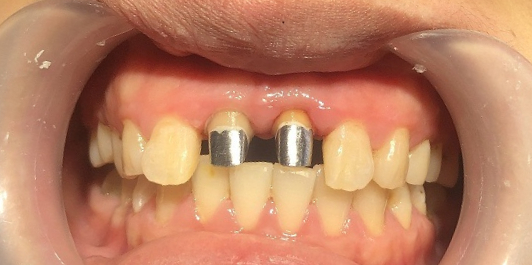

全冠修复种类:

1.铸造金属牙冠:全部由金属铸造出来的牙冠,色泽和不锈钢、金属差不多,现在主要用于后牙修复,因为前牙比较注重美观,一般不会用,只会用到后牙做修复。

桩核冠与全冠修复